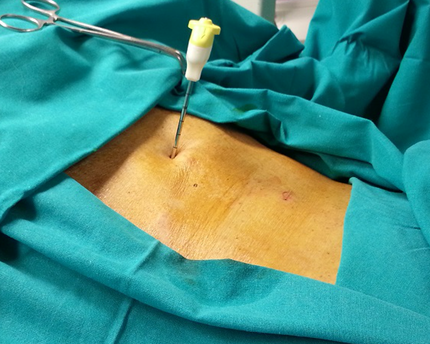

ОПЕРАЦИЯ ВЫПОЛНЯЕТСЯ ЧЕРЕЗ ПРОКОЛ КОЖИ ПОД КОНТРОЛЕМ ЭЛЕКТРОННО ОПТИЧЕСКОГО ПРЕОБРАЗОВАТЕЛЯ

Проведение вертебропластики не подразумевает выполнения классических оперативных доступов в костным структурам. Вся манипуляция выполняется хирургом через прокол кожи, тем самым оставляя приемлимым косметический результат, что для некоторых пациентов может быть одним из немаловажных вопросов.